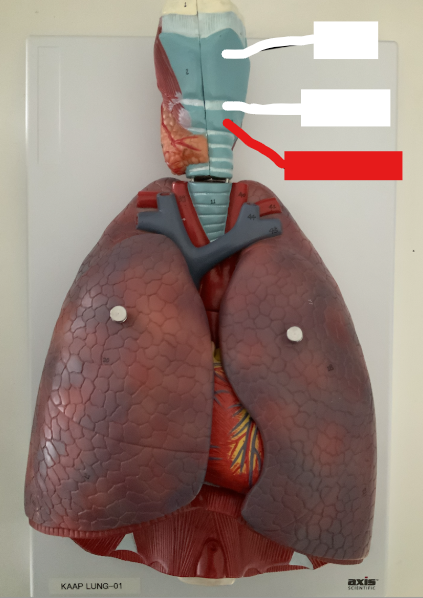

What structure is this?

Thyroid Cartilage

What structure is this?

Cricothyroid Ligament

Cricoid Cartilage

What structure is this?

Epiglottis

What structure is this?

Trachea

What structure is this?

Tracheal Cartilage

The pharynx

What structure is this?

Larynx

What are the three laryngeal cartilages?

epiglottis, cricoid and thyroid cartilage